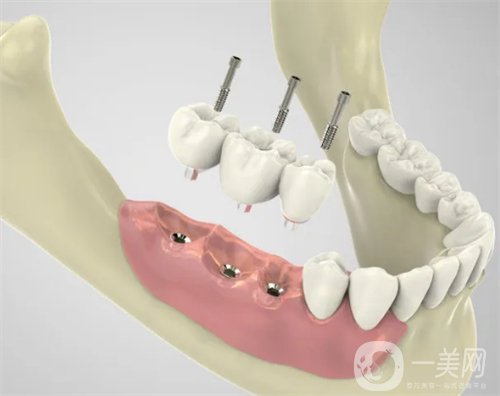

三、天津愛齒口腔種植牙案例

我掉的那顆牙齒是因為我咬東西的時候不小心要掉了一半,后來牙齒松動直接就掉了。估計大家可能還會嘲笑我怎么這么沒出息,吃東西都可以把自己的牙齒給割掉,其實我想說的是實在是太寸了,真的沒有想到我的牙齒會這么脆弱。有一個牙洞實在是太別扭了,到口腔醫(yī)院讓醫(yī)生給我看了一下,說是可以做種植牙這個手術來補上之前那個牙洞。醫(yī)生簡單的和我說了一下,種植牙是一個怎么樣的手術,以及手術的大概過程和術后修復。

做完種植牙已經四個半月的時間了?,F(xiàn)在我的那顆牙齒早就已經種好了。在種好了之后我特別小心的使用著,可牙齒醫(yī)生還告訴我這顆牙齒是特別堅固的,比我自己長的那些牙齒還要兼顧,讓我放心好了,現(xiàn)在的我吃東西一切都恢復了正常。我感覺*近幾天都讓我長胖了,畢竟每天胡吃海塞的。